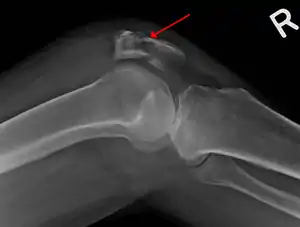

| A fracture of the patella seen on a lateral view | |

Comminuted fracture of patella